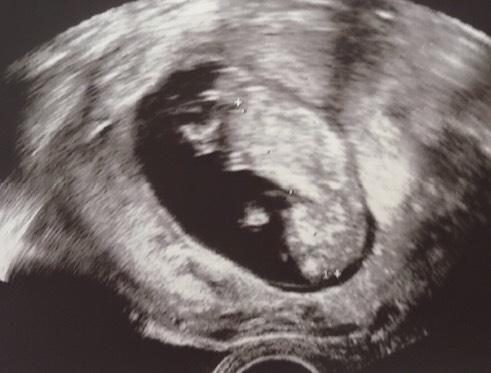

Entschuldige meine späte Rückmeldung!! Alles in Ordnung! Lt Messung bin ich 11+3 - eigentlich aber 12+0 aber die Ärztin meinte das ist im Rahmen und sie will den ET erstmal stehen lassen

Erst hat es geschlafen aber dann ordentlich rumgetanzt. Bildchen ist auch dabei - es machte ein Kopfstand